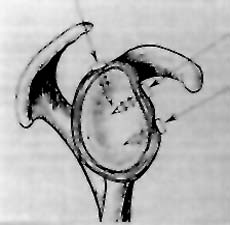

Snyder y col (13) clasifica a las lesiones del LABRUM-ANTERO-POSTERO-SUPERIOR'-< (SLAP) en 4 TIPOS, (Fig. 4).

Fig. 4: S. L A. P. Clasificación de SNYDER. En 4 tipos..

TIPO 1: DESGARRO DEL MARGEN LABRAL pero se mantiene firme a la glenoides.

TIPO 2: DESGARRO DEL MARGEN LABRAL en el borde superior del labran-biceps.

TIPO 3: DESGARRO EN ASA DE BALDE DEL LABRUM SUPERIOR.